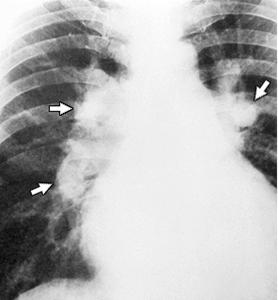

Rx cord-pulmon: circulatie pulmonara 'incarcata' cu ramurile AP dilatate in hiluri si extremitati 'retezate' avind periferie mult mai clara decat normal, bombare a conului arterei pulmonare, semne de hipertrofie VD

HTP secundara incipienta (DSA) HTPS severa (DSA Eisenmengerizat)

Imagine Rx. de profil cu HVD Aspect CT de HTP primara